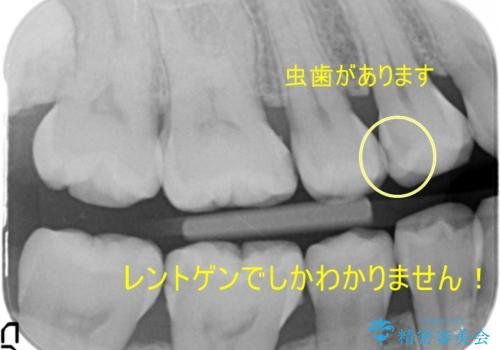

- 右下の奥歯にインプラントを入れたいと来院。

抜歯から時間が経っており、骨が十分あったためすぐにインプラントを入れることが可能でした。骨も補う必要がありませんでした。

インプラントの術式は比較的単純で、難しくないですが、予後を見据えて角化歯肉を増やす手間をかけることが大変重要です。

長期的な予後を見据えた治療をしてもらえる病院を、慎重に選んでいただくことをお勧めします。